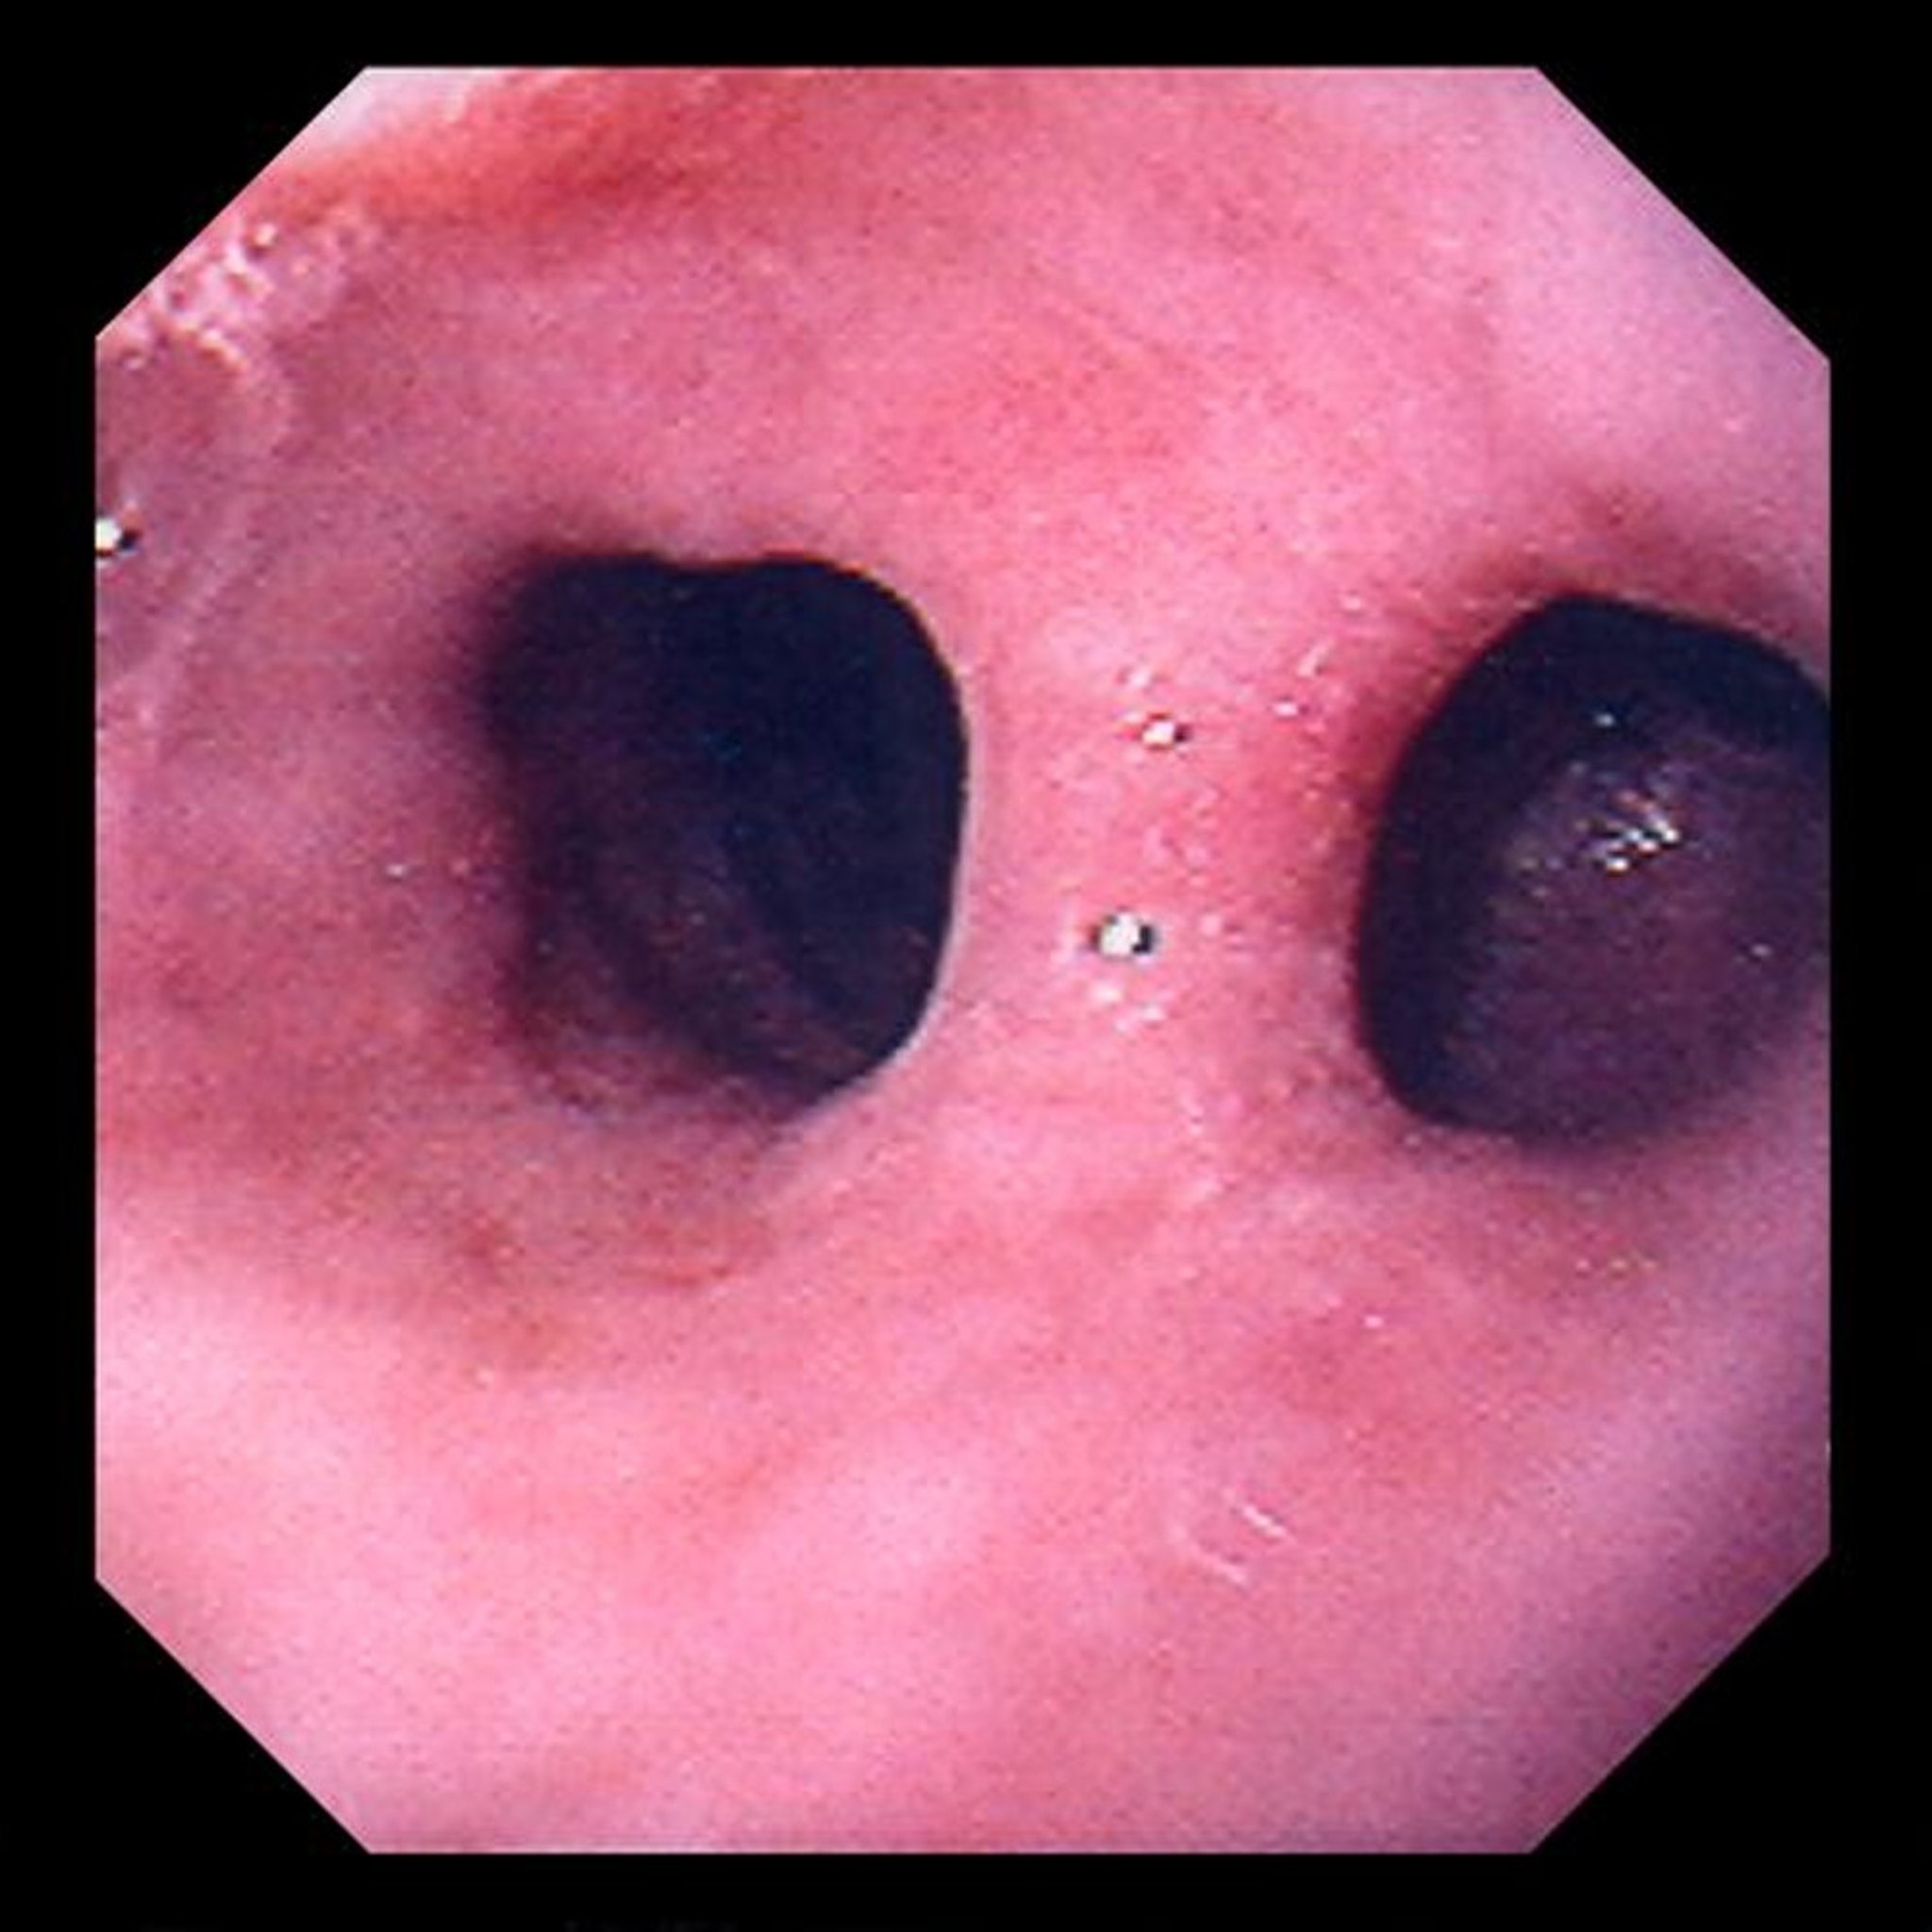

Traction Diverticulum

Traction diverticula are midesophageal outpouchings of mucosa and submucosa caused by motility disorders or by traction resulting from mediastinal processes. In this image, the diverticulum is to the right of the esophagus and gives the appearance of a double lumen.

Image provided by David M. Martin, MD.